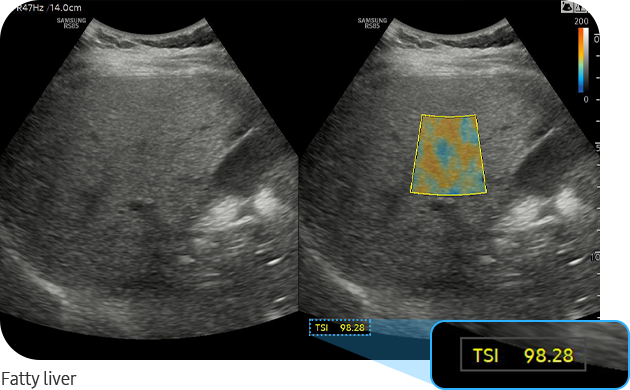

TSI™ (Tissue Scatter Distribution Imaging) is a tool that quantifies the scattered signal distribution based on backscattered signals. Scattering, the reflection of ultrasound waves in multiple directions not affected by their entry angle, produces speckle patterns in ultrasound images and this changes the distribution of backscattered ultrasound signals based on the scattering intensity.